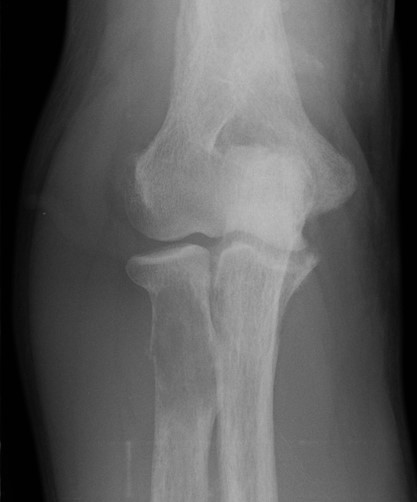

Proximal Tibial Lytic Epiphyseal Lesion XrayTibia biopsy 1

Tibial Shaft LesionTibia biopsy 2

Distal Fibular Lucent LesionTibia biopsy 3

Tibia and fibular

Tibia: direct medial approach directly onto bone

Fibula: direct lateral or through peroneus, anterior to intermuscular septum